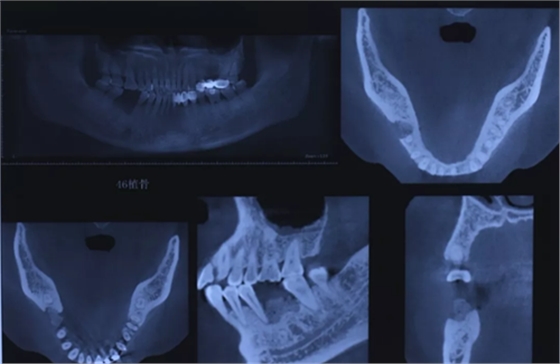

7、术后CBCT检查

术后CBCT显示拔牙窝内充满植骨材料。

(摄于2016年8月31日)